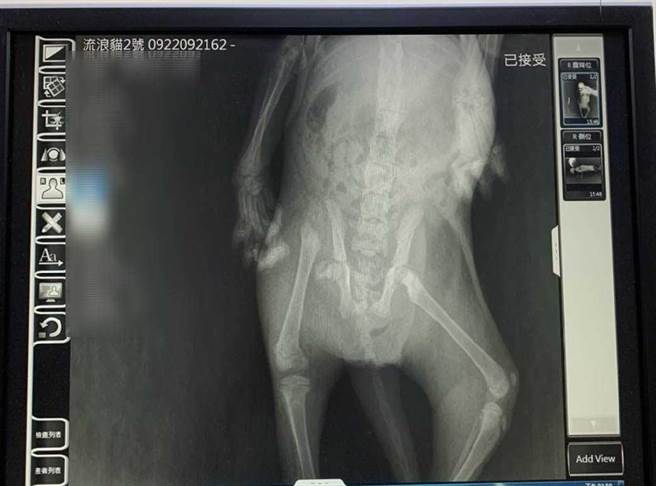

後來李小姐將小貓帶到新北市動保處尋求協助,為小貓操刀的獸醫師林洋演盼對,受傷原因很可能是車禍撞擊所致,但因為手術無法單獨完成,所以找來了雙和動物醫院院長趙安基及熟悉骨科的獸醫師李建沛共同討論,最後在3位醫師合作耗時2個多小時的手術下,終於成功治療小貓的傷勢。